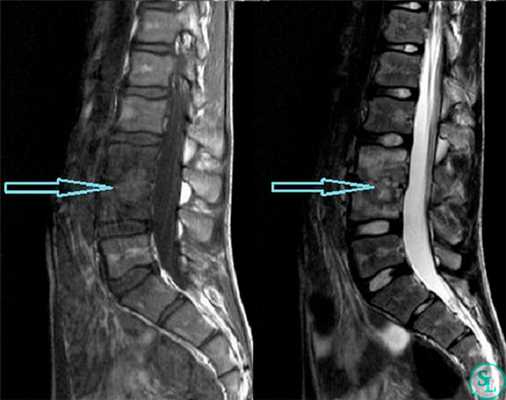

В диагностике заболеваний позвоночника большей популярностью пользуется магнитно-резонансная томография (или точнее «ядерно-магнитно-резонансная»), более безопасная и чувствительная, чем жесткое рентгеновское излучение. На снимках костные структуры получаются черными, но мягкие ткани, наполненные водой, передают все оттенки серого и белого цветов. Это позволяет обнаруживать мельчайшие объекты (узелковые образования, инфильтрации) и отслеживать динамику развития абсцесса.

- МРТ позвоночника. Определяется снижение интенсивности сигнала на Т1-взвешенных снимках и его повышение на Т2-взвешенных изображениях, деформация межпозвоночных дисков, структурные изменения тел позвонков. Чувствительность магнитно-резонансной томографии достигает 96%, точность - 94%, поэтому ее считают «золотым стандартом» диагностики.

Исследование мягких тканей позвоночника с помощью рентгенографии дает неоднозначные результаты: явственно различить нарушения целостности межпозвоночных дисков не удается. Гнойное расплавление и формирование абсцессов можно определить только по размыванию контуров замыкательных пластинок и искажению очертаний тел позвонков.